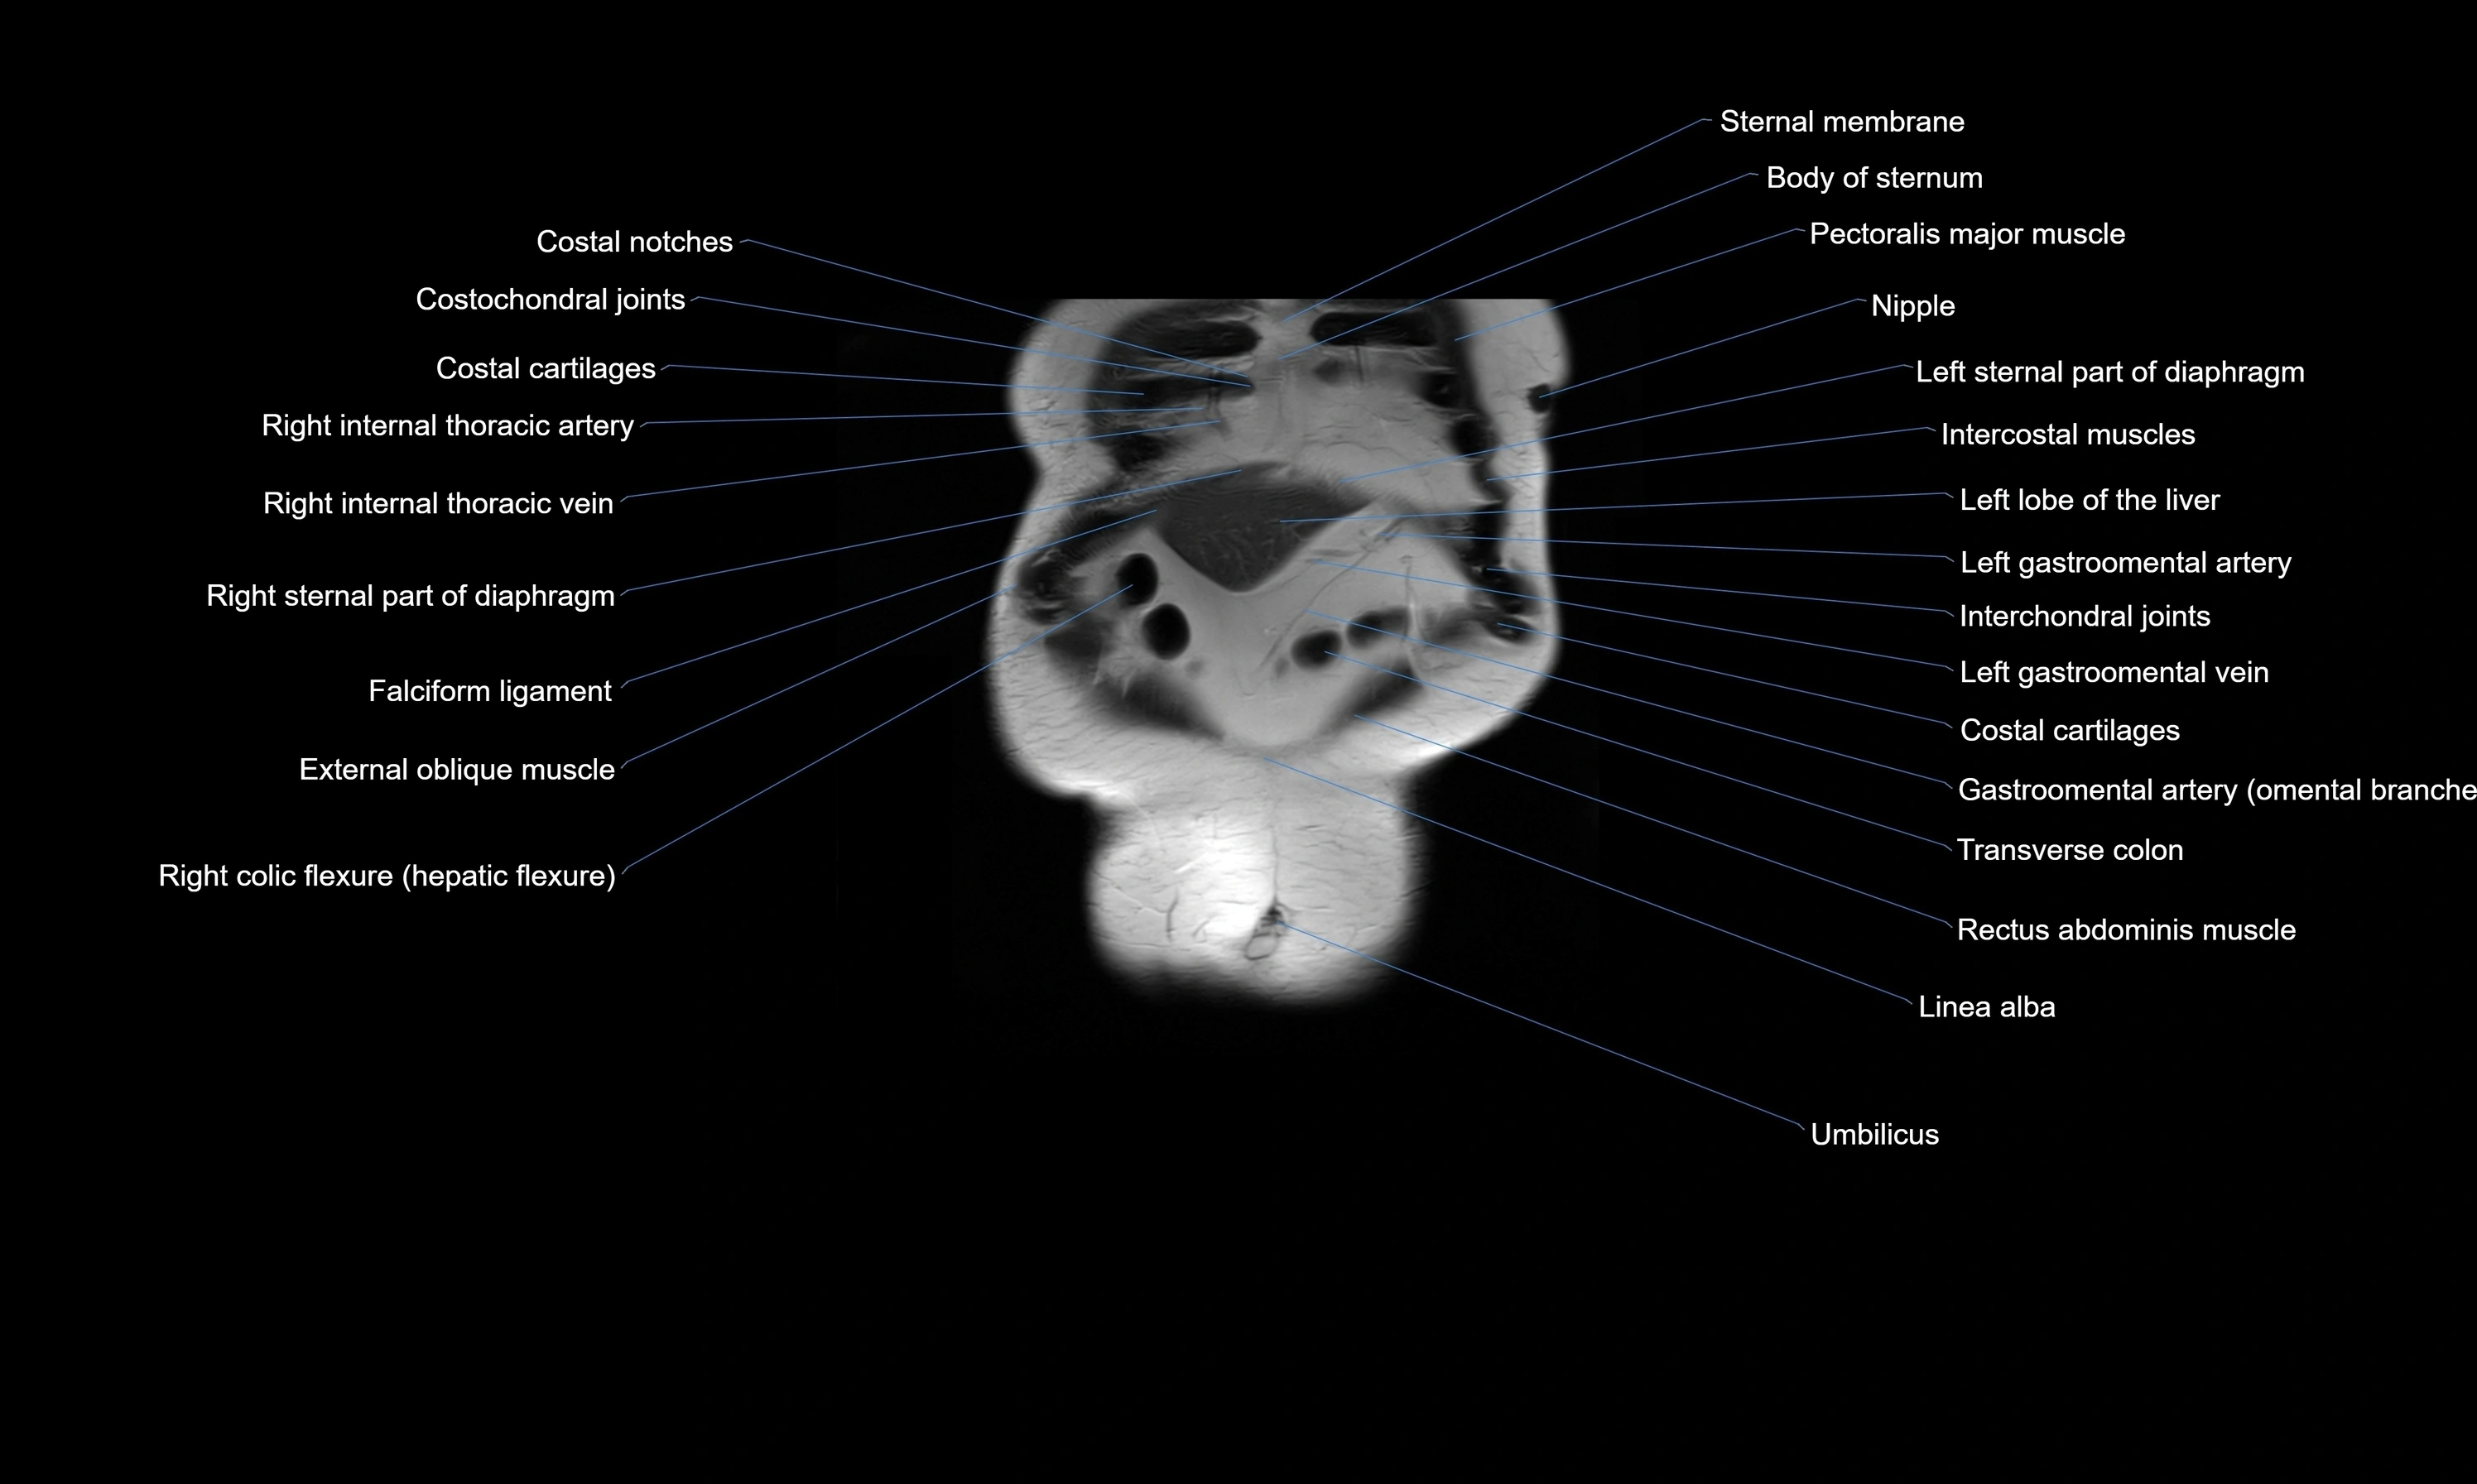

MRI images